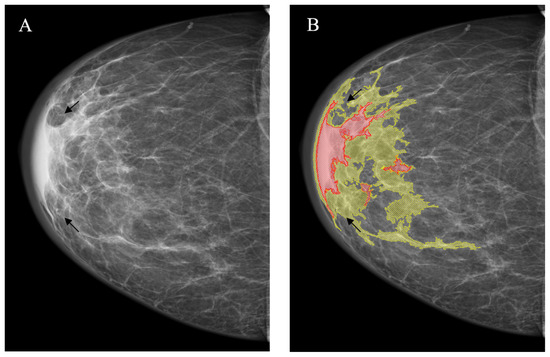

- Egoshin, I.; Pasynkov, D.; Kolchev, A.; Kliouchkin, I.; Pasynkova, O. A segmentation approach for mammographic images and its clinical value. In Proceedings of the 2017 IEEE International Conference on Microwaves, Antennas, Communications and Electronic Systems (COMCAS), Tel-Aviv, Israel, 13–15 November 2017; pp. 1–6. Available online: https://ieeexplore.ieee.org/document/8244764 (accessed on 10 March 2022). [CrossRef]